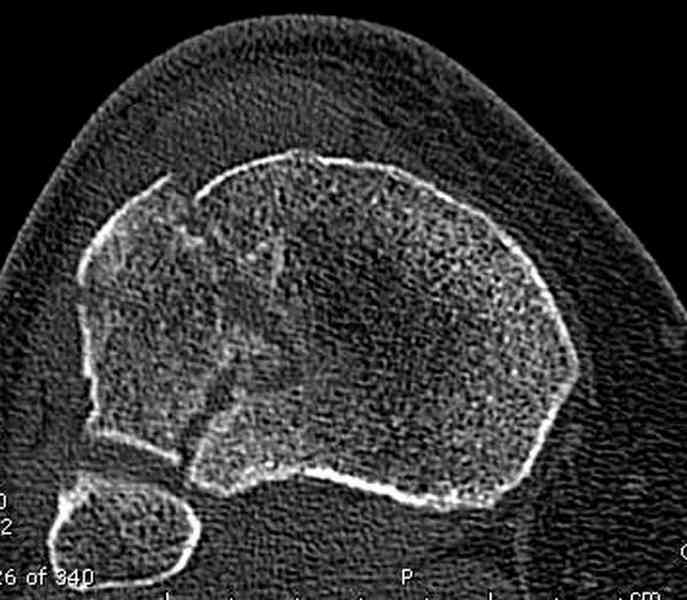

Для внутрисуставных переломов необходимо идеальное сопоставление, а такая задача без КТ срезов усложнится. Только КТ надо делать после дистракции сустава, иначе нельзя получить объективную информацию.

Около 60% переломов тибиал плато характеризуются мягкоткаными повреждениямм - разрывы суставной капсулы, связок и менисков. Мениск повреждается спереди со стороны перелома.

Основная задача в лечении околосуставных переломов является создание солидного базиса в субхондральной зоне. Пластина подпорка (Butress) или субхондральные перкутанные шурупы в виде плота (Raft) для ранних движении.